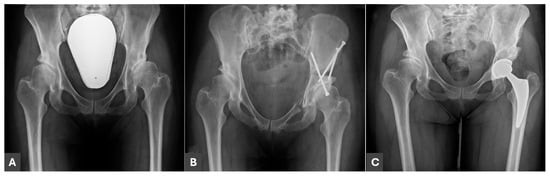

Impact of Prior Periacetabular Osteotomy on Total Hip Arthroplasty Outcomes in Patients with Developmental Dysplasia of the Hip